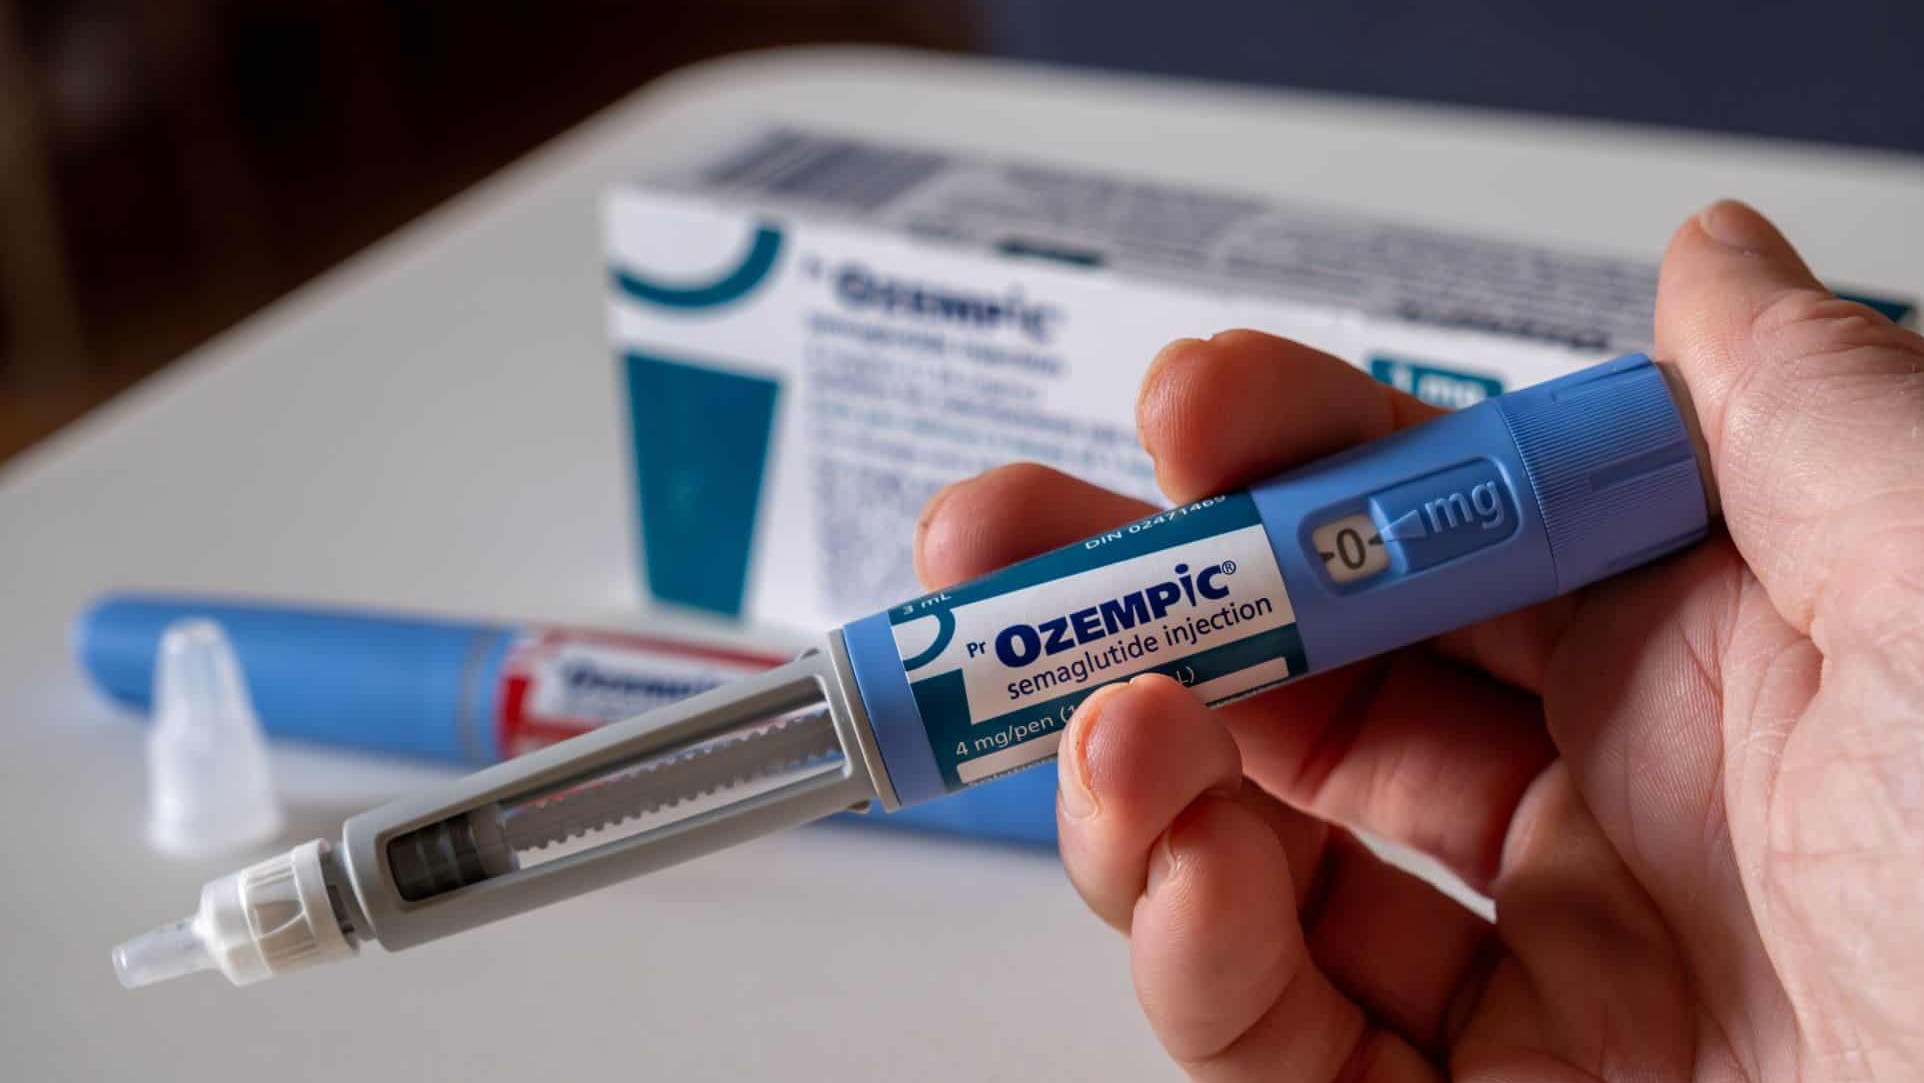

Ler maisOzempic e Mounjaro podem ampliar desigualdades, dizem cientistas

Medicamentos à base de semaglutida e tirzepatida, como Wegovy, Ozempic e Mounjaro, vêm transformando o tratamento da obe...

Ler maisOzempic e Mounjaro podem ampliar desigualdades, dizem cientistas

Medicamentos à base de semaglutida e tirzepatida, como Wegovy, Ozempic e Mounjaro, vêm transformando o tratamento da obe...

Veja os destaques do Olhar Digital News desta terça-feira: EMS anuncia preços da primeira caneta nacional de semaglutida...

Veja os destaques do Olhar Digital News desta terça-feira: EMS anuncia preços da primeira caneta nacional de semaglutida...